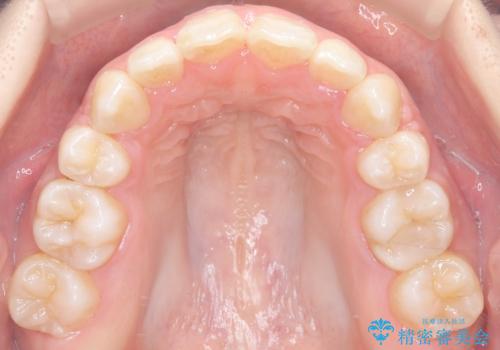

- 前歯のデコボコ(叢生)と、上下の歯が閉じない開口を主訴にご来院されました。精密な検査の結果、歯が並ぶスペースが不足しており、特に奥歯の咬み合わせが安定していないことが開口の原因と判明。患者様と相談し、上下左右の小臼歯を抜歯することでスペースを確保し、審美ワイヤー矯正で全体を整える治療計画を立案しました。これにより、見た目の改善だけでなく、機能的な咬み合わせも獲得することを目指します。

今回の矯正治療では、歯が並ぶスペースを確保するため、上下左右の小臼歯を抜歯しました。装置には目立ちにくい審美ワイヤーを使用し、見た目に配慮しながら治療を進めました。抜歯によってできたスペースを利用して歯を並べ、前歯のデコボコを解消。同時に、歯列全体を動かすことで、上下の歯がきちんと閉じる開口も改善しました。治療期間は約2年間。治療の結果、コンプレックスだった前歯のデコボコと開口が解消され、整った美しい歯並びと、しっかり咬める機能的な咬み合わせを獲得していただけました。